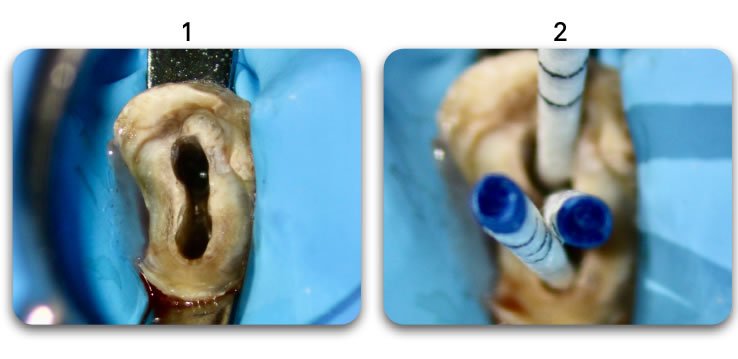

- Biolight® DRILL-FREE adapts to all shaped canals, while conserving all remaining healthy tooth structure.

- There is no need to drill out portions of canals to accommodate post spaces.

- Easily place multi-posts in multiple canals as the post bends with the natural canal shape.

YES. At first glance, Biolight® DRILL-FREE appears to be perfectly adapted for use in oblong canals, however, since the concept behind the product is to provide support around the periphery of the canal walls, it is ideal for ALL shapes of canals.